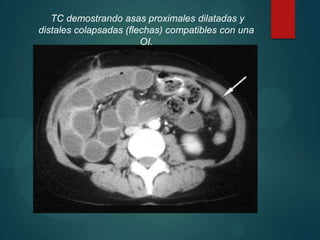

TC demostrando asas proximales dilatadas y

distales colapsadas (flechas) compatibles con una

OI.

TC demostrando asasproximales dilatadas y distales colapsadas (flechas) compatibles con una OI.